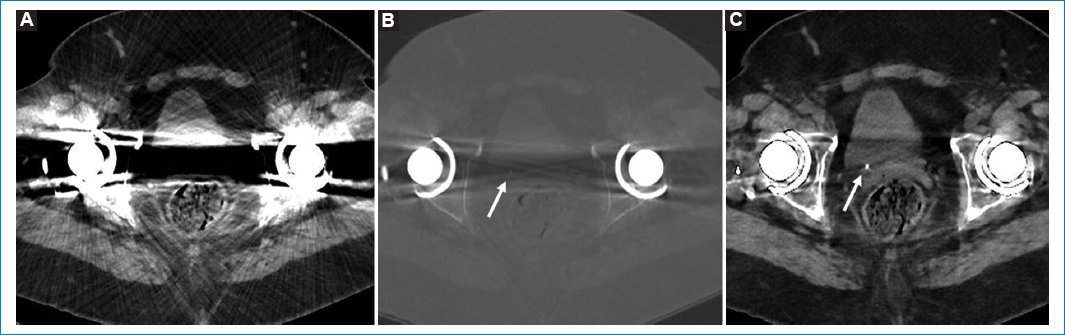

En la ecografía se visualiza una dilatación ureteropielocalicial derecha, sin identificar la litiasis, por lo que se decide completar el estudio con TC de abdomen y pelvis sin contraste intravenoso. En la TC de abdomen, el artefacto metálico producido por ambas prótesis de cadera imposibilita la visualización correcta de la causa de la obstrucción, lo que impide un correcto tratamiento de la paciente en función de los hallazgos. Gracias al algoritmo de reconstrucción para reducción del artefacto metálico (MAR, metal artifact reduction), finalmente se visualiza una litiasis de 3 mm en el uréter yuxtameatal (Fig. 1).

Figura 1. TC de pelvis sin reconstrucción MAR en ventana de partes blandas (A), con ventana ampliada (B) y con el algoritmo MAR (B). Se muestra el artefacto metálico producido por ambas prótesis de cadera que inicialmente impide la visualización de la litiasis en la ventana partes blandas. Con anchura de ventana ampliada se logra identificar una imagen hiperdensa, pero no permite su correcta caracterización por falta de contraste tisular. Tras la reconstrucción MAR, se visualiza bien (localización y tamaño de la litiasis, diagnóstico diferencial con flebolito).